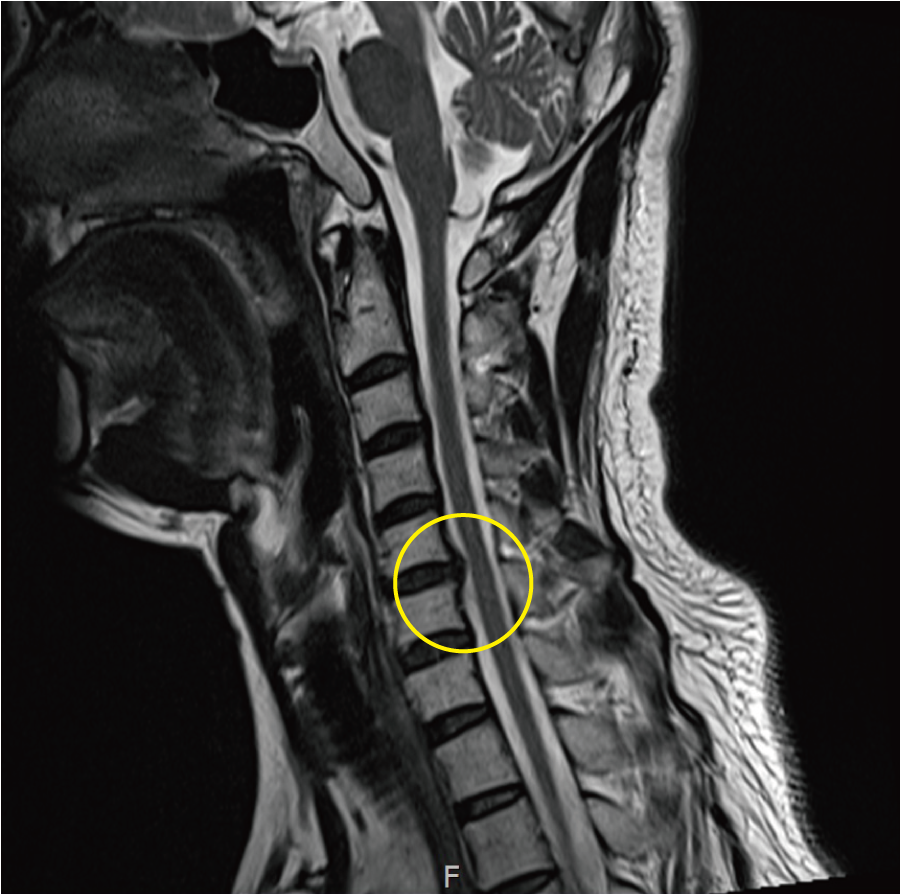

목디스크의 주요 증상

목디스크의 가장 일반적인 증상은 목 부위의 통증입니다. 통증은 지속적이거나 간헐적으로 나타날 수 있으며, 목과 어깨를 움직일 때 더욱 심해질 수 있습니다. 특히 장시간 컴퓨터 작업이나 스마트폰을 사용하면 이러한 통증이 심해질 수 있습니다.

다음으로 나타날 수 있는 증상은 팔이나 손으로 방사되는 통증입니다. 목디스크로 인해 신경이 눌리면 팔로 통증이 전달될 수 있습니다. 이럴 경우 팔과 손의 감각이 떨어지거나 통증이 발생할 수 있습니다.

셋째, 마비감이 느껴질 수 있습니다. 목디스크가 신경을 압박하게 되면 어깨나 팔, 손에 불편한 감각이 나타나거나 마비되는 경험을 할 수 있습니다. 이는 일상생활을 아주 힘들게 만들 수 있습니다.